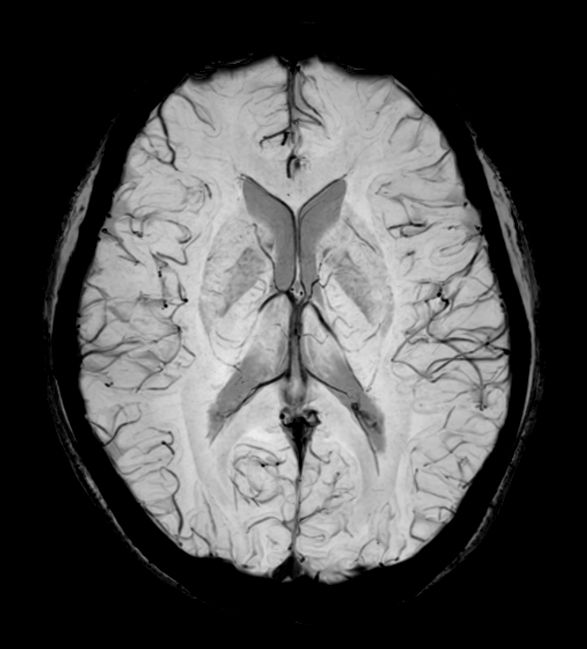

3D T2w TSE (Axial reformat)

Fast and high quality 3D imaging for Brain and IAC. AI based SmartSpeed is utlized to shorten scan time without compromise in image quality. Advanced 3D TSE imaging technique are used to acquire high resolution data in multiple directions in only one single scan. Addition of DRIVE enhances fluid visualization for IAC imaging, while providing high contrast-to-noise and high signal-to-noise ratio simultaneously. SWIp 3D susceptibility weighted brain imaging is added, offering a high sensitivity to enhance contrast for deoxygenated (venous) blood or calcium deposits.